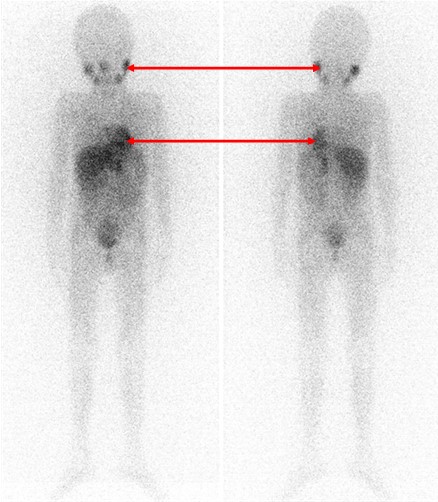

Одним из наиболее информативных специфических методов топической диагностики нейробластом является сцинтиграфия с метайодбензилгуанидином (МЙБГ), меченным 123I. МЙБГ по своей химической структуре сходен с катехоламинами в организме. Это вещество концентрируется в тех опухолях, которые вырабатывают катехоламины. МЙБГ метят радиоактивным изотопом йода (например, 123I) в безопасной для жизни дозе, и готовый препарат внутривенно вводят в кровоток. Накапливаясь в клетках опухоли, он дает излучение. Эти сигналы регистрирует специальная камера и переводит их в изображение. Таким образом, метод позволяет выявить не только первичную опухоль, но и наличие регионарных и отдаленных метастазов (рис. 7).

Рис. 7. Сцинтиграфия с метайодбензилгуанидином (визуализируется первичная паравертебральная опухоль с метастазами в кости черепа)